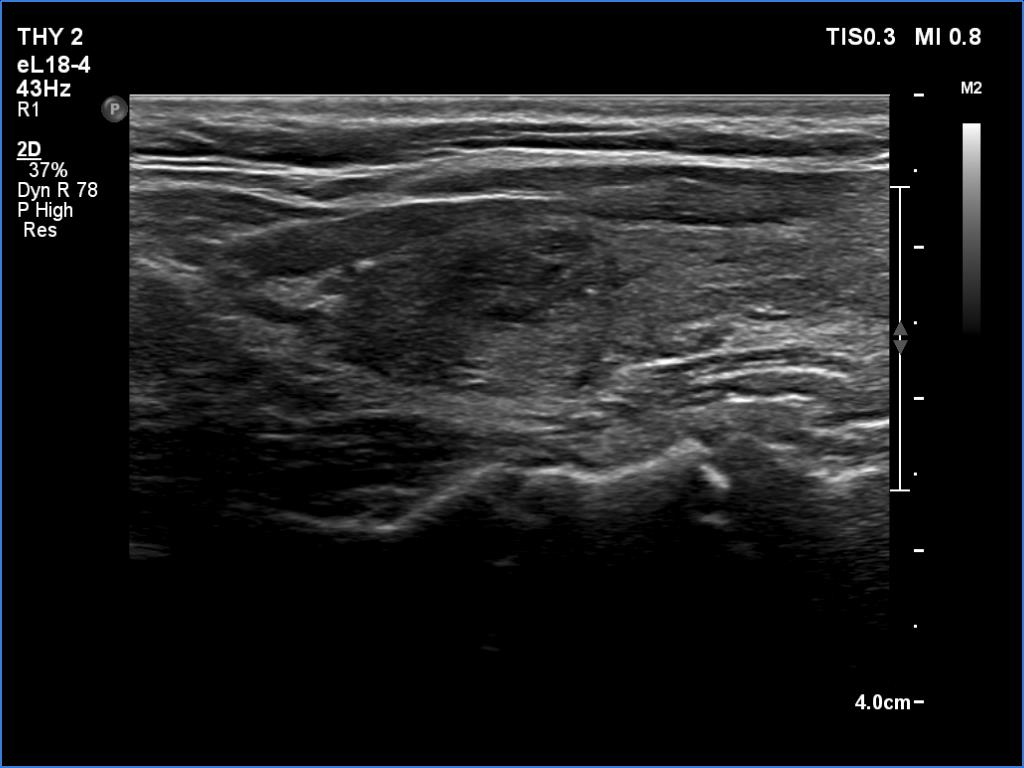

Second examination 3 months later (ultrasonographic picture 7)

Left lobe, longitudinal scan. Although the echogenicity of the lobe has not normalized, the degree of hypoechogenicity has decreased.